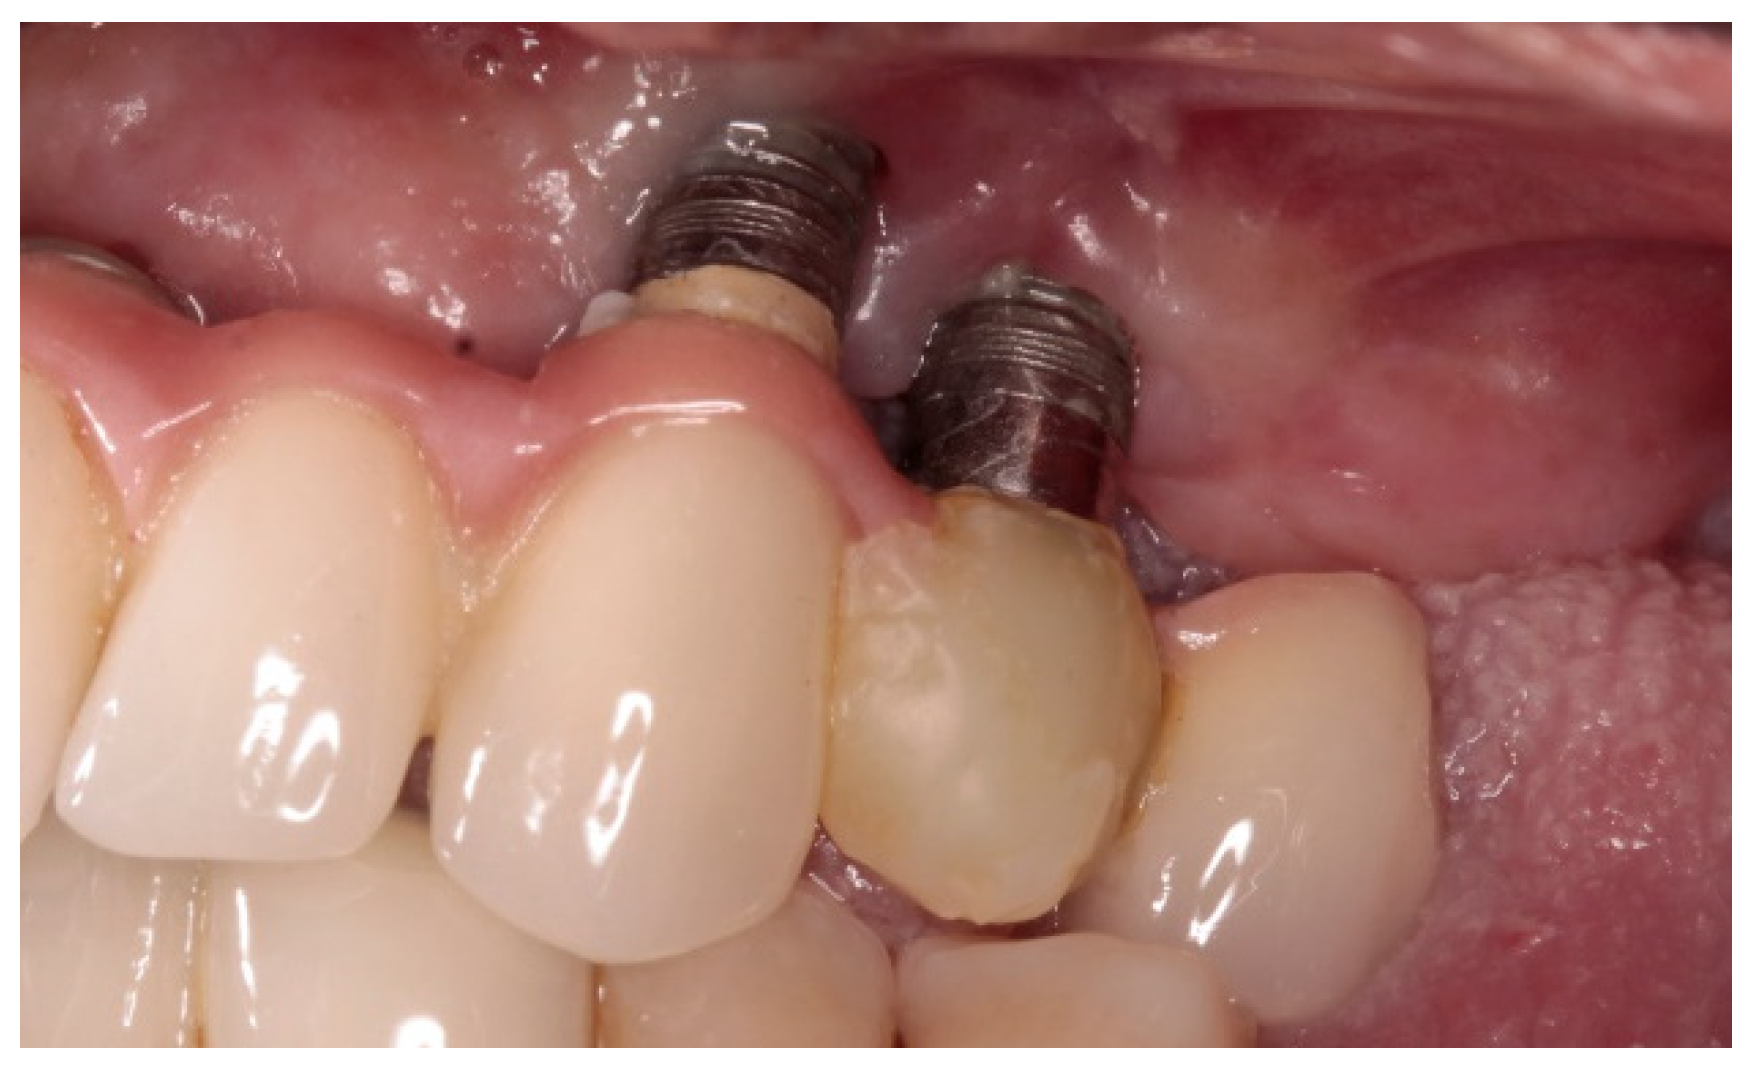

Variables related to the subject were collected; such as age, gender, tobacco consumption and history of periodontitis, as well as variables related to the implants. The main parameter was the presence of keratinized mucosa (KM), as well as the width of KM measured in millimeters in the mid-buccal surface of the implants with a periodontal probe CP 15 from Hu-friedy® (Frankfurt, Germany). The absence of KM was considered when there was non-keratinized mucosa at the gingival margin of the implant (Figure 1). Recession (the apical migration of the gingival margin) was measured in the mid-buccal surface from the cervical margin of the crown, where the gingival margin was located at the time of prosthesis placement. Other parameters were: Silness and Löe plaque index (Figure 2); probing depth using a plastic periodontal probe (Premier®) (at six points: mesiobuccal, buccal, distobuccal, mesiopalatal, palatal and distopalatal) (Figure 3); bleeding (its presence or absence was measured); suppuration (its presence or absence was measured); and bone level (distance, in mm, between the implant shoulder and the base of the defect) using Rhinoceros® software (Robert Mcneel & Associates, Seattle, WA, USA) on the parallelized radiographs. Bone loss due to peri-implantitis was considered when a crater-shaped image was observed surrounding the implant (taking as reference the most apical area of the crater) (Figure 4), accompanied by clinical signs such as bleeding or suppuration. The years since prosthesis placement were also noted. All data were collected by a single operator who visually analyzed the esthetics of the peri-implant tissues.

Figure 1.

Absence of keratinized mucosa implant 2.3.